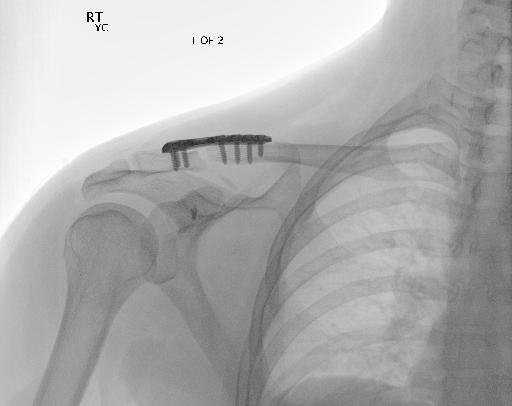

Bone 이미지 데이터 350장 중 Fracture 이미지 50장, Implant 이미지 50장, Bone 이미지 50장을 선별했다.

train과 val은 라벨링을 해야한다. 어제 라벨링을 했었지만, Fracture는 좀 넓게 잡고, Implant는 최대한 여러개로 쪼개는 느낌으로 라벨링을 다시했다.